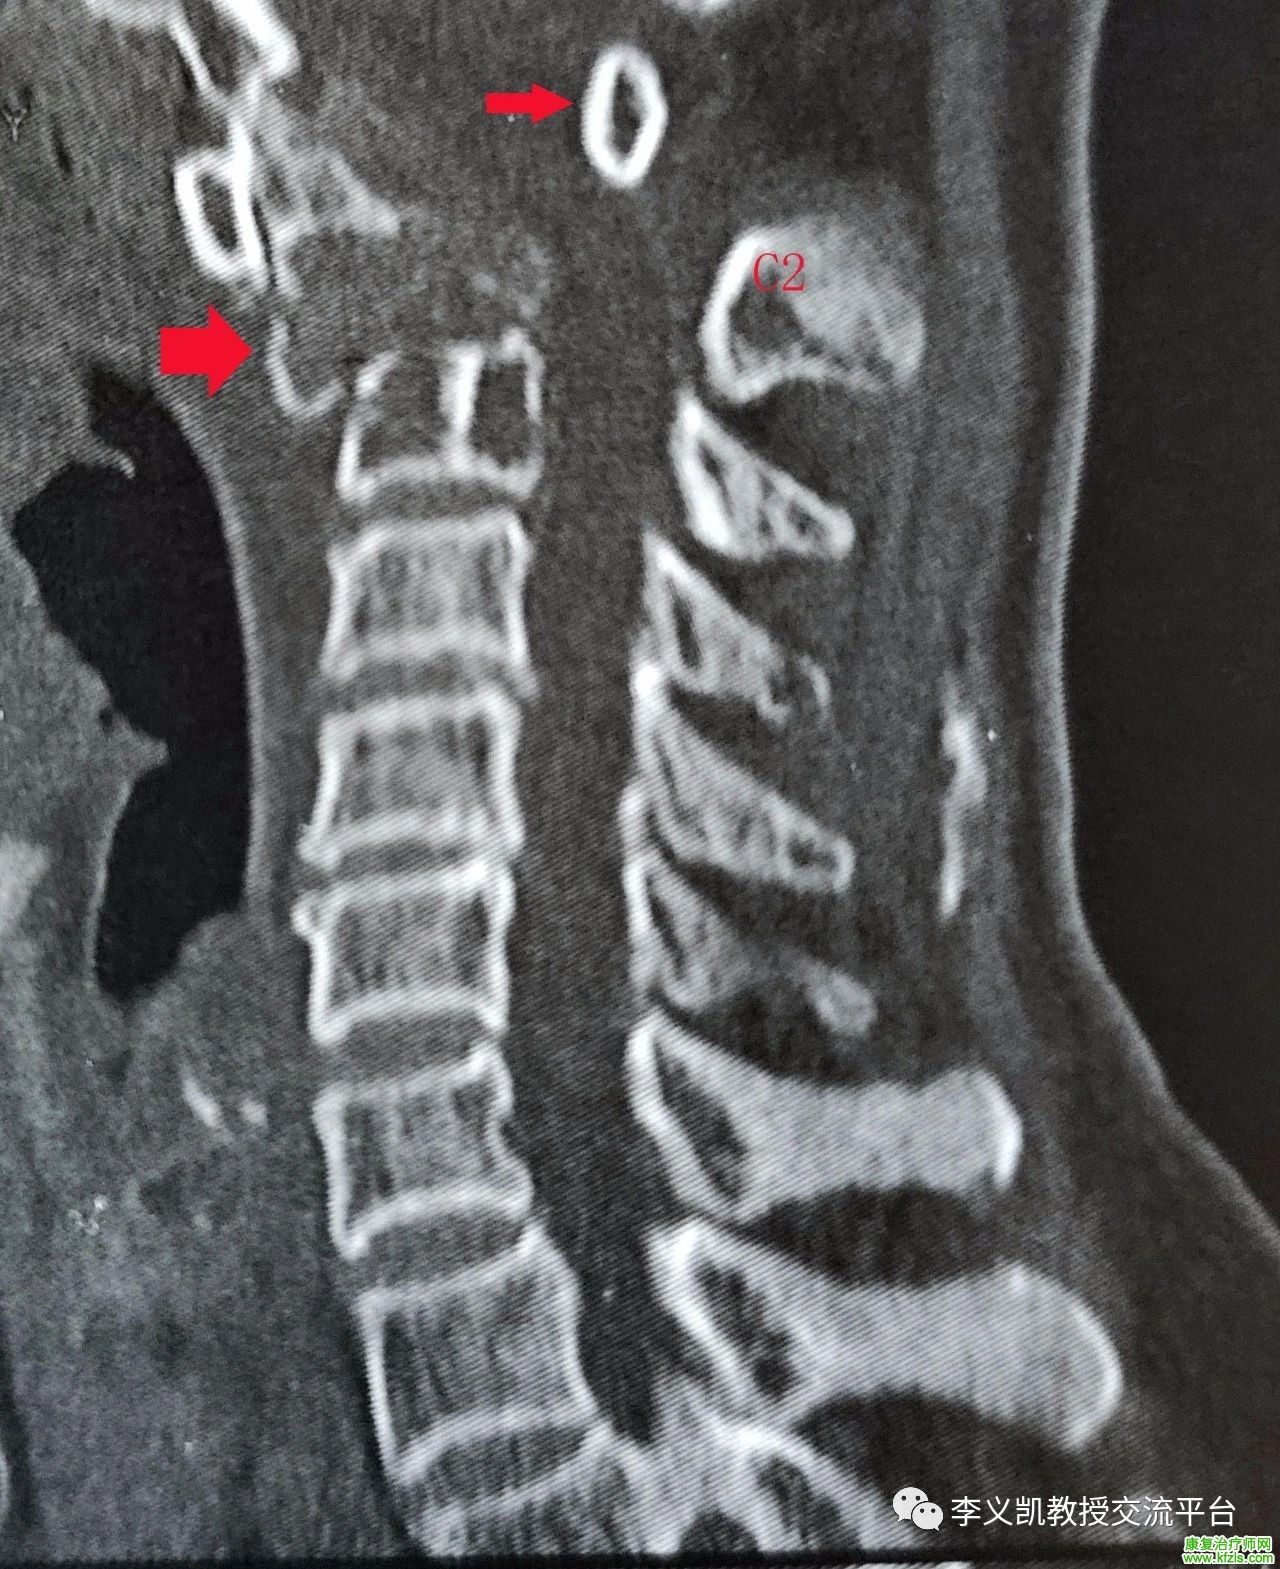

作为一名专业的物理治疗师,平时会遇到很多颈肩腰腿疼的患者,手法治疗成为最常用的方式之一,但是平时一定要谨慎下手,转载自李义凯教授的交流平台的文章,本病例很常见,有警示作用,值得认真阅读下,这是一例C3骨折脱位向后移位明显的病例。

本例患者的颈椎矢状位CT片可见,其C3骨折脱位向后移位明显,占据椎管空间,患者右侧霍夫曼阳性,左侧阴性,颈活动度稍差。患者的病情十分危险,建议及早手术复位内固定,解除对脊髓的压迫,以免压迫时间过久伤及脊髓,造成难以恢复的损害。图1中最左侧的箭头是寰椎的前结节,中间的箭头为齿状突,右边的箭头为寰椎的后结节。